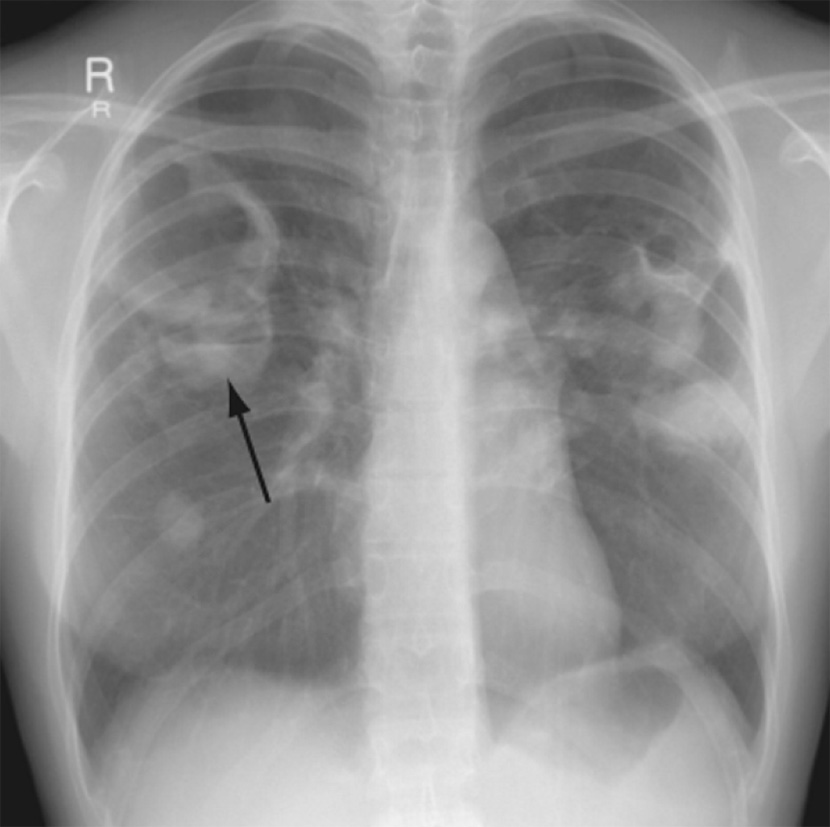

Волчаночный пневмонит (люпус-пневмонит) характеризуется одно- или двусторонними участками интерстициальной инфильтрации по типу «матового стекла», которые могут сочетаться с альвеолярной инфильтрацией. Эта патология встречается гораздо реже. Отметим, что при системной красной волчанке может возникать легочное кровотечение, при этом на рентгенограмме легких определяются распространенные инфильтраты (рисунок 1). Кроме этого, при системной красной волчанке в нижних отделах легких могут обнаруживаться фиброзные изменения, однако выраженный фиброз и «сотовое легкое» развиваются редко.

Рисунок 1. Поражение легких при системной красной волчанке. На рентгенограмме, выполненной у больного с кровохарканьем, обусловленного обширным легочным кровотечением, в прикорневой зоне и среднем легочном поле справа определяется высокоинтенсивная, нечетко ограниченная инфильтрация, также в нижней доле слева визуализируется начальная инфильтрация. Слева отмечается небольшой плевральный выпот

Рисунок 4. Острый пневмонит при системной красной волчанке. В нижнем и среднем отделе правого легкого определяется усиление рисунка с образованием ретикулярных теней и неоднородной инфильтрации. Гистологическое исследование биоптата показало васкулит и кровоизлияние